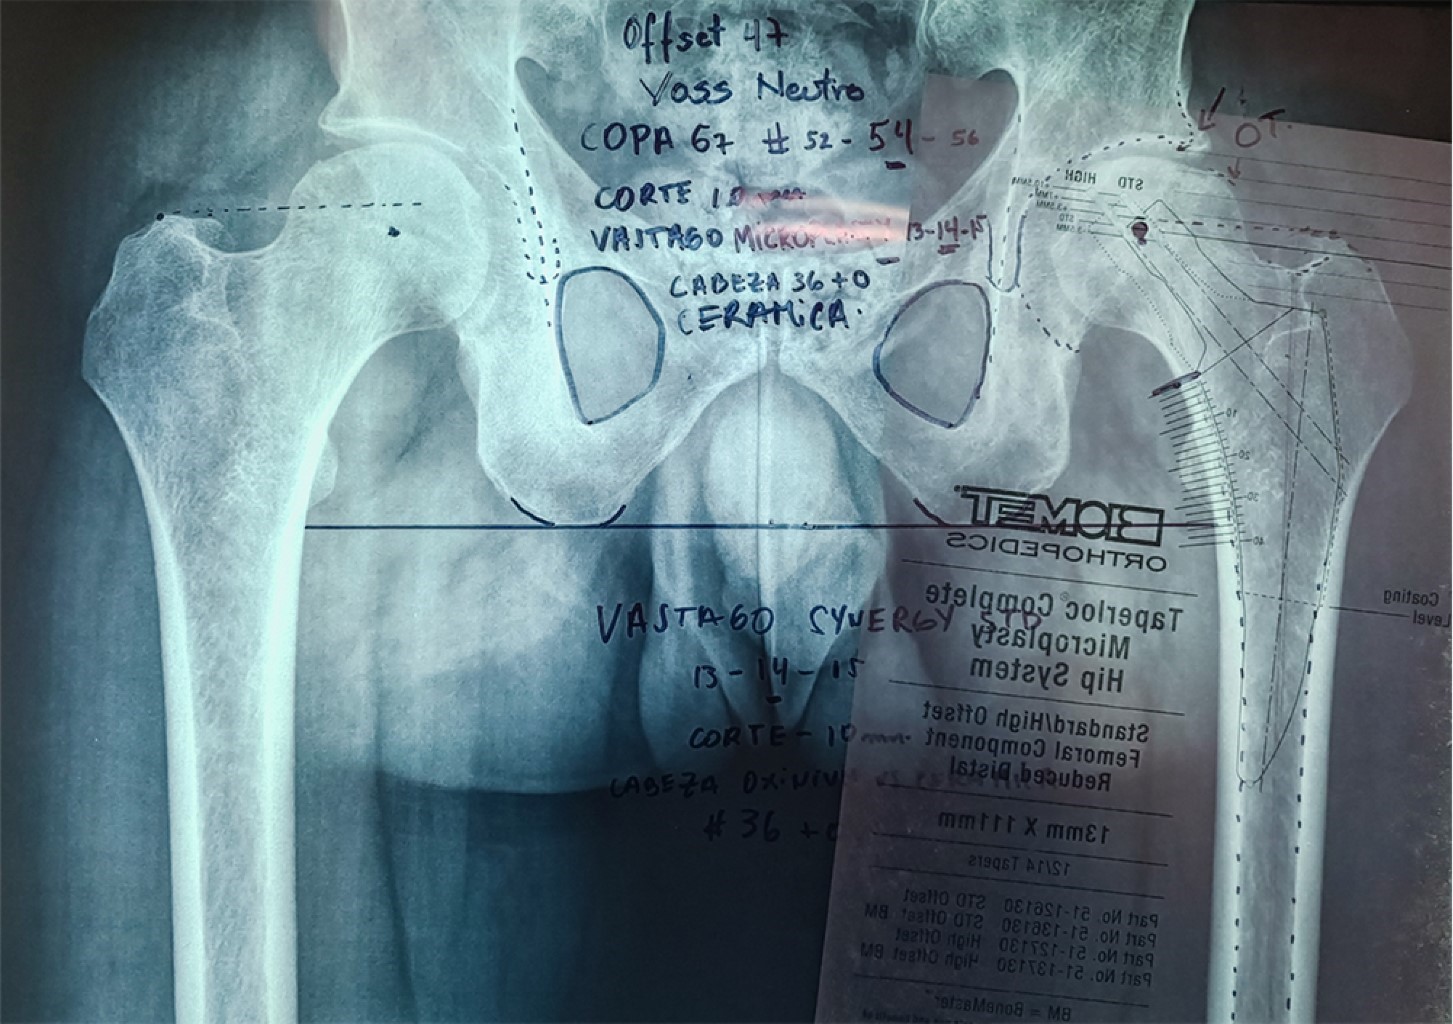

Figure 2